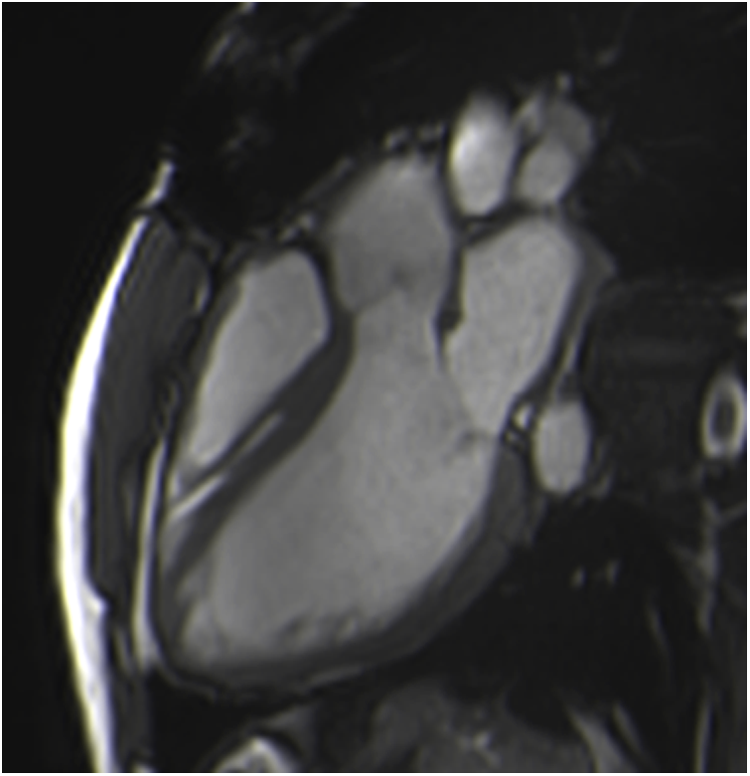

Cardiac balanced steady-state free precession (bSSFP) sequences, with their high signal-to-noise ratio and precise discrimination between blood and tissue, allow biological valve delineation and orifice area planimetry for stentless bioprosthetic valves (Figure 3). For surgical stented prostheses, orifice area planimetry is more difficult due to CMR stent-related artefacts (Figure 4). A spoiled echo sequence, less prone to artefacts from ferromagnetic metals, may generate better image quality. Border discrimination of the valve leaflet is almost impossible for degenerated prostheses due to leaflet calcifications, causing additional signal void.

Figure 3

Visualization of the prosthetic orifice of a stentless aortic valve (freestyle) (A) obtained from two orthogonal planes: three-chamber view (B) and coronal LVOT (C). The red line indicates the slice position. Visualization of the leaflets allows easy planimetry.